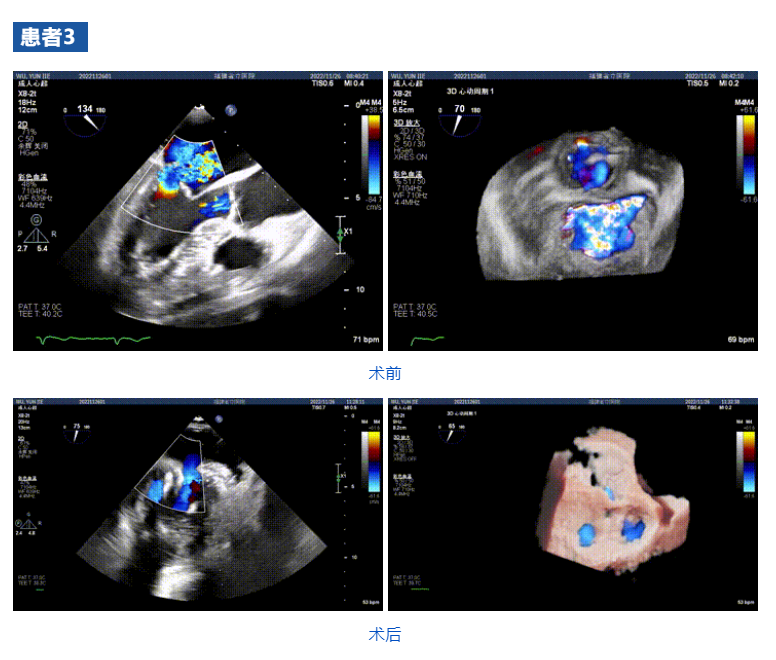

接受治療的三例患者均為器質性重度二尖瓣反流(DMR)患者,術前超聲提示二尖瓣后葉脫垂伴4+反流,左室舒張功能減退。郭延松教授攜同團隊成員陳新敬副教授和洪景宣、方明程、楊清勇主治醫(yī)師、心外科丁杭主任以及超聲科賴寶春、葉振盛主治醫(yī)師共同進行病情討論。考慮到患者高齡、基礎疾病多、STS評分高,為外科手術極高?;颊?,不適合進行外科開胸二尖瓣手術,因此決定為患者實施經導管緣對緣修復介入術(JensClip經導管瓣膜夾系統(tǒng))。

在浙江大學醫(yī)學院附屬第二醫(yī)院王建安教授團隊的支持下,手術經股靜脈-房間隔入路,采用全身麻醉插管,在TEE和DSA引導下完成房間隔穿刺。置入JensClip瓣膜夾系統(tǒng)后,在左房調整瓣膜夾的位置和軸向,后進入左室,在TEE引導下捕捉二尖瓣前后瓣葉,并關閉瓣膜夾。經TEE反復確認手術效果后最終鎖定并釋放瓣膜夾。術后即刻超聲顯示瓣膜夾位置穩(wěn)定,功能良好,二尖瓣反流由術前4+減少至微量,手術圓滿成功。